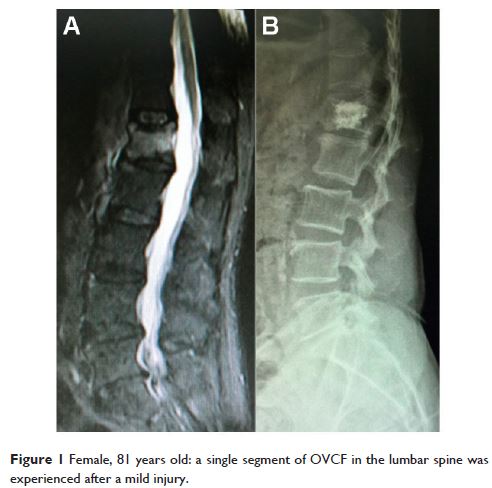

- 作者:Liang Zhang, Qiang Wang, Lin Wang, Jian Shen, Qiwei Zhang, Changtai Sun